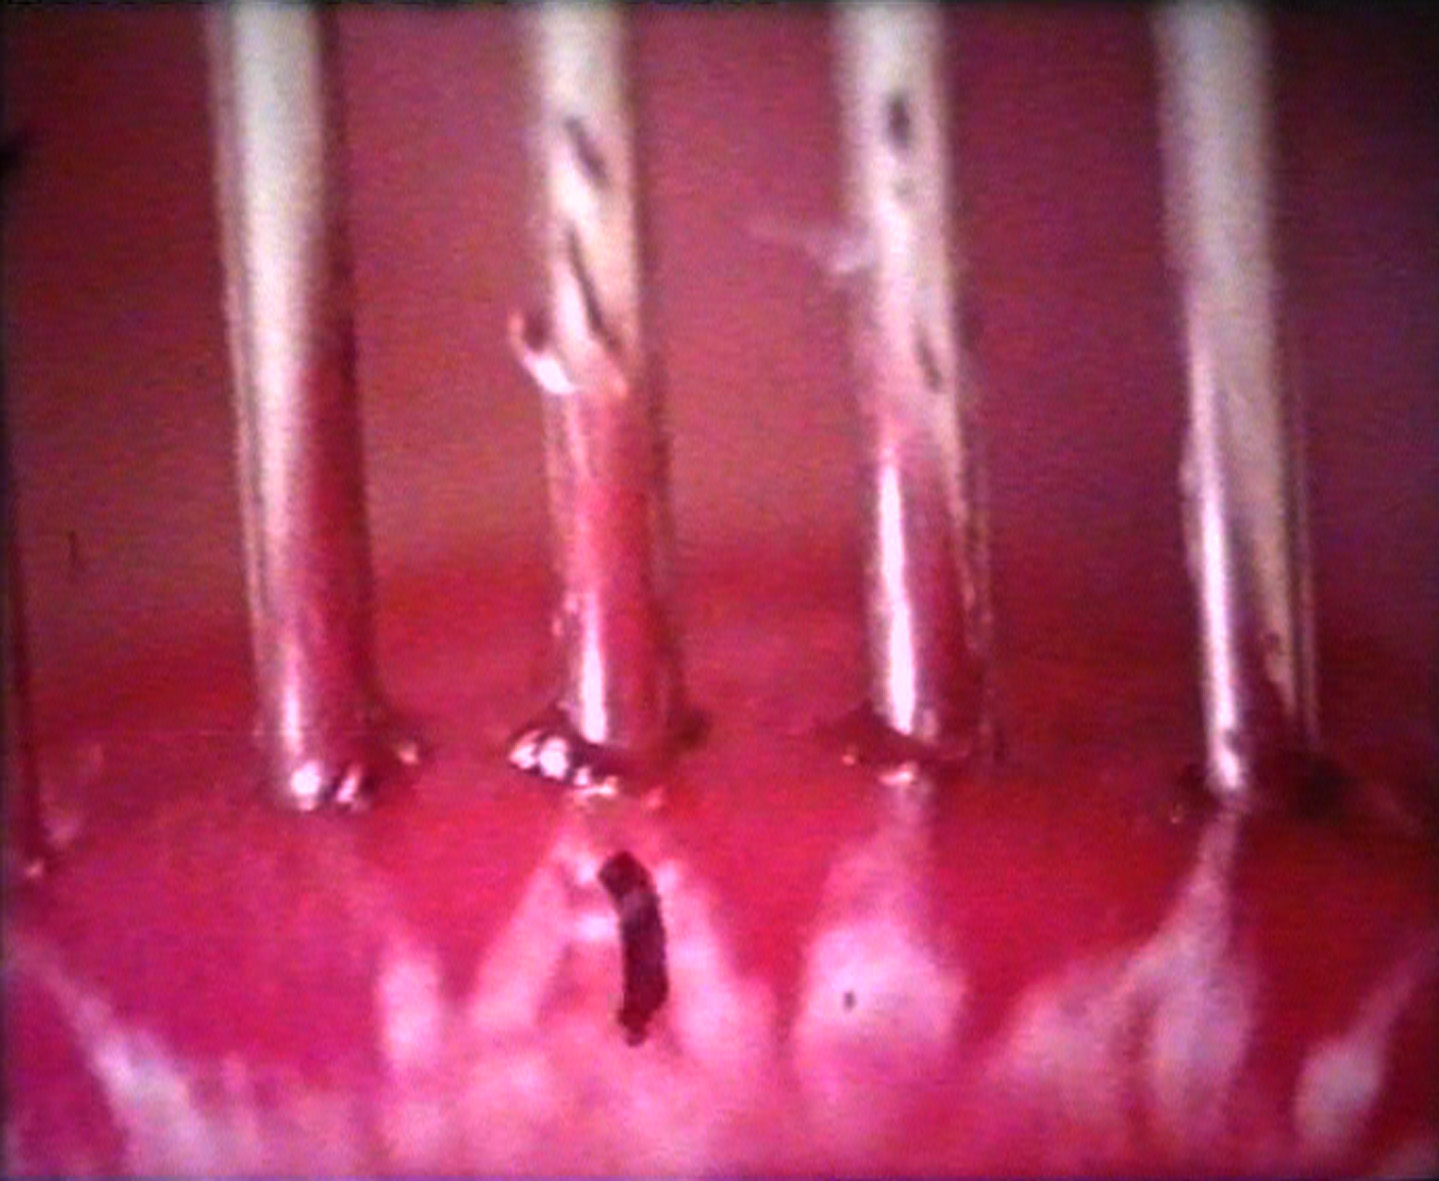

The Vegetarians

Peter Rubin | 14' | Nederland | -

Een eenvoudig etentje van zorgvuldig gefotografeerde receptuur met griezelige close-ups. -